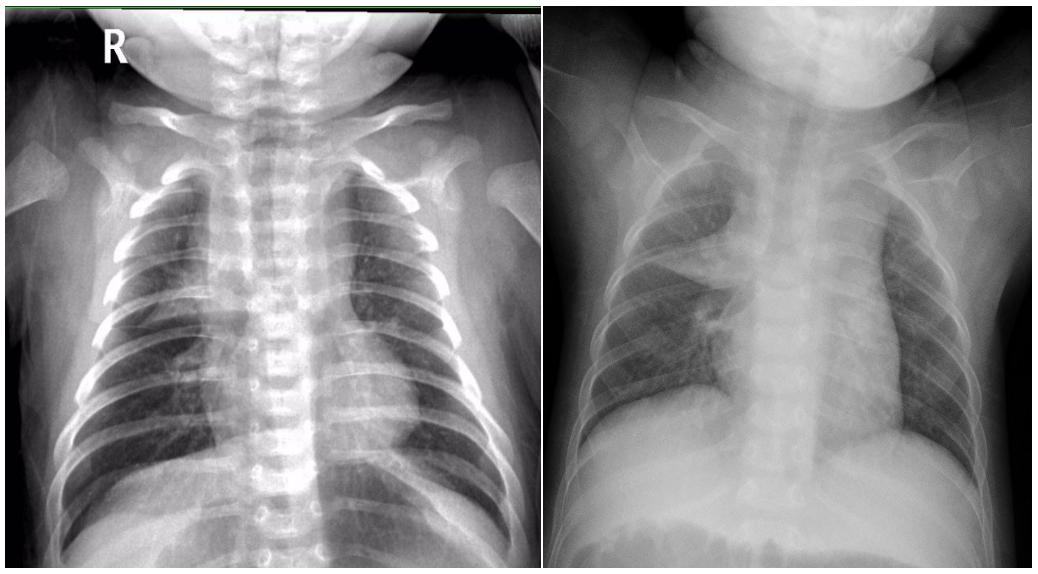

5、巨大肿块形:单侧或对侧,致密,外带密度逐渐减低,占据整个上肺野及部分中肺野,下缘清晰锐利,外缘模糊。如下图8所示。

图8示:巨大肿块样的胸腺影

大致掌握了胸腺影的特征后,再来看看年轻规培医师所遇到的两组X线影的区别(上滑问题处,点击空白查看答案)。